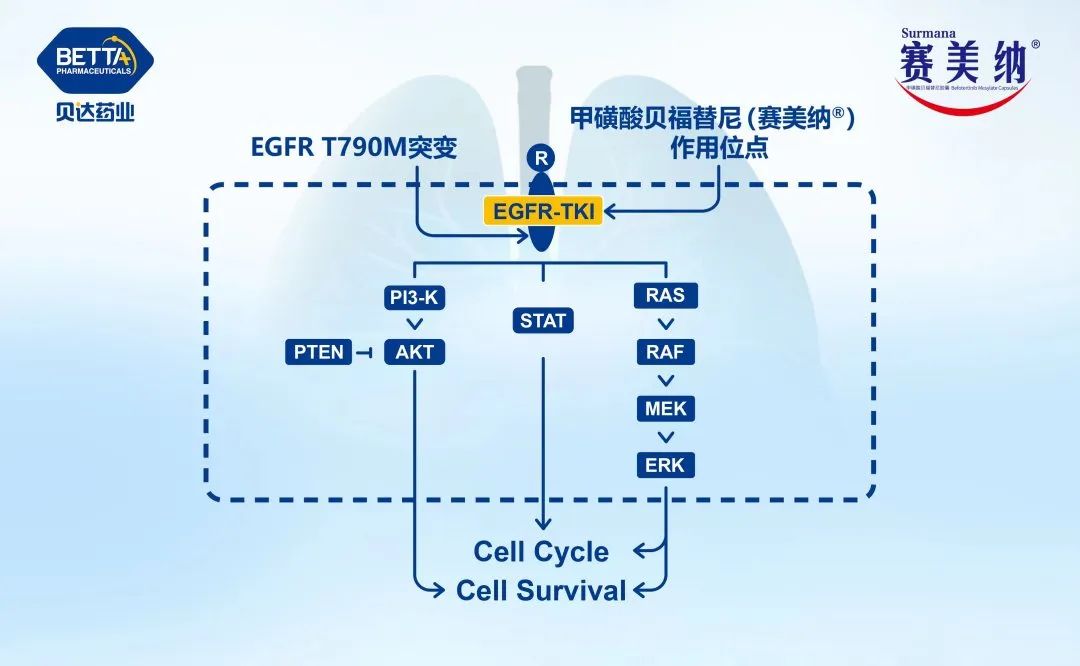

何志勇主任介绍,经过再次对肿瘤活检和检验检测,发现李先生仍然存在EGFR突变的肿瘤克隆。

“可能肿瘤还依赖EGFR信号通路,提高三代EGFR-TKI给药浓度是可能的有效方法之一。”

何医生介绍,三代EGFR-TKI伏美替尼由于化学结构上的优化,具备提高药物浓度而不增加副反应的可能,国内外有相似的研究报道。因此,建议李先生开始口服“双倍剂量伏美替尼”靶向治疗。令人欣喜的是,1个月后复查,李先生肺部及肝脏转移灶较前明显退缩,疗效评价达到部分缓解。